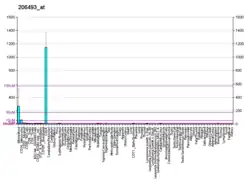

Integrin alpha-IIb is a protein that in humans is encoded by the ITGA2B gene. ITGA2B, also known as CD41, encodes integrin alpha chain 2b. Integrins are heterodimeric integral membrane proteins composed of an alpha chain and a beta chain. Alpha chain 2b undergoes post-translational cleavage to yield disulfide-linked light and heavy chains that join with beta 3 to form a fibrinogen receptor expressed in platelets that plays a crucial role in coagulation. Mutations that interfere with this role result in thrombasthenia. At least 38 disease-causing mutations in this gene have been discovered.[5] In addition to adhesion, integrins are known to participate in cell-surface mediated signalling.[6]